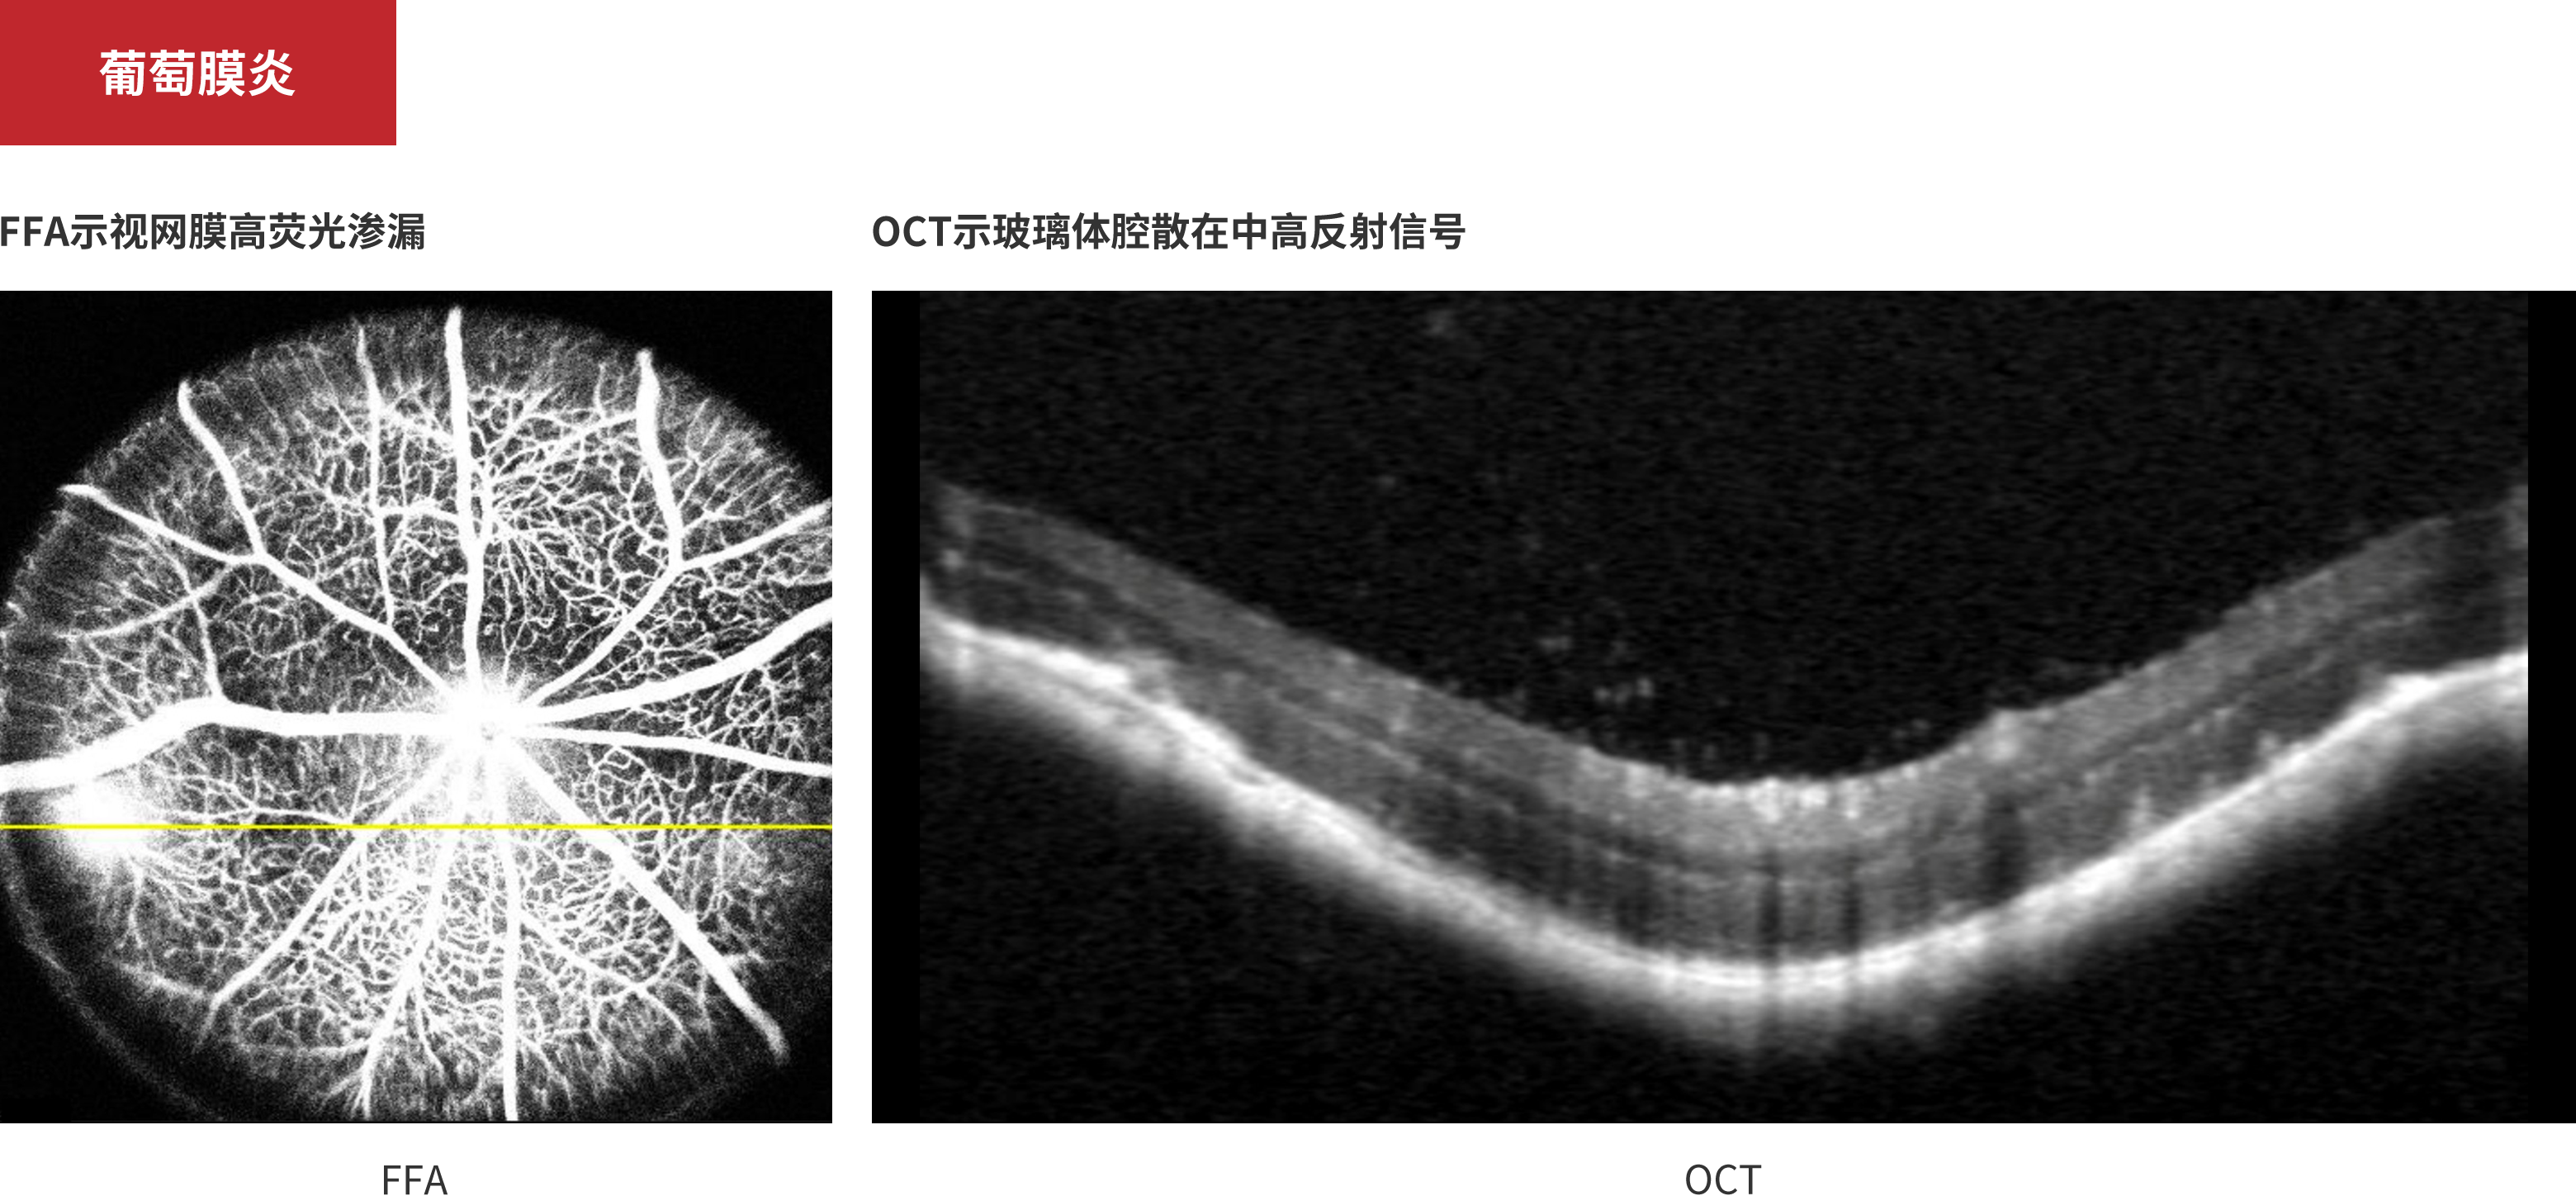

葡萄膜炎